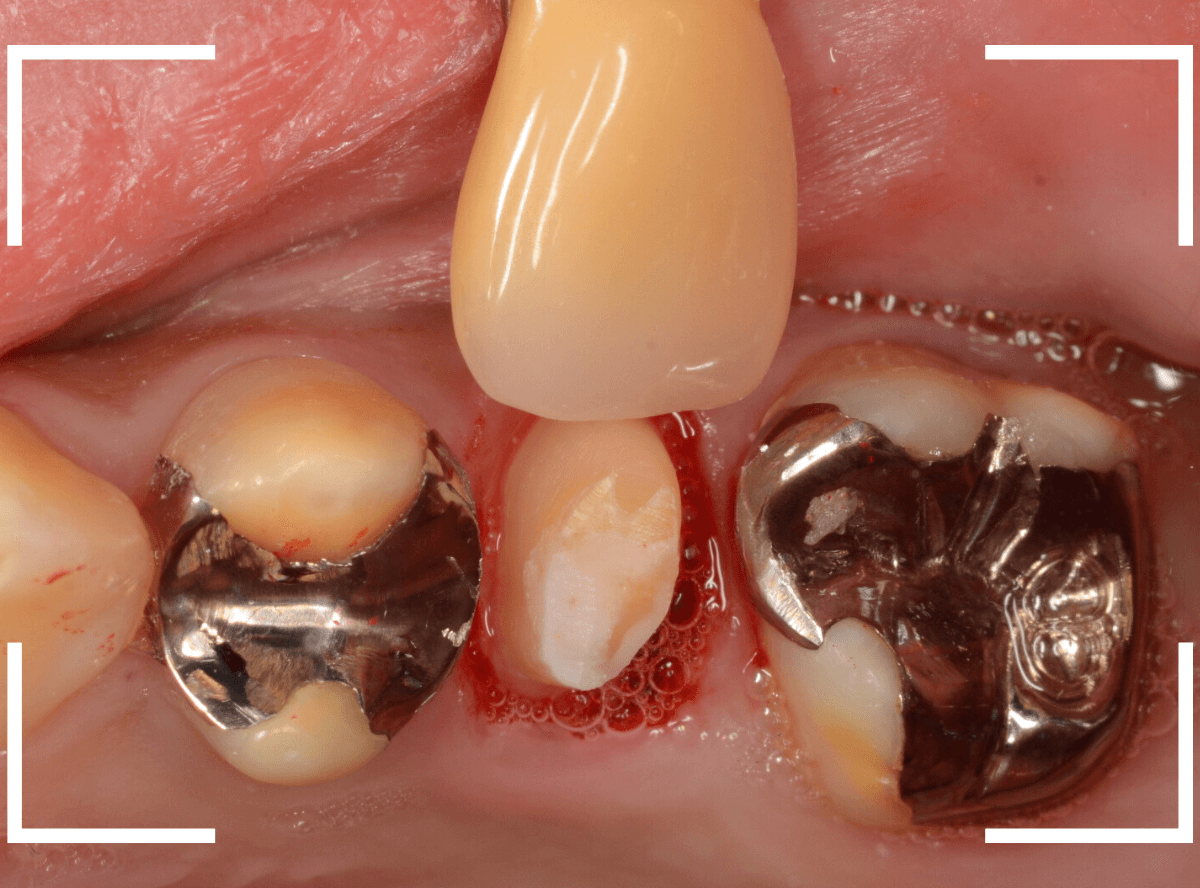

さし歯を作る前にまず、歯の補強(コア)処置をします。

セラミック・インレーを除去し、歯の内部もある程度削ります。

歯の内側をコアで補強後、さし歯で被せるために、歯全体を削ってトリミングし、型取りします。

模型上で、精密に製作します。

最終setした状態です。

見た目も問題なく、患者さんにも満足いただけました。

このように、神経を取ってしばらく経った歯は思ったよりももろくなって破折しやすいため、全体を覆うさし歯で修復する事が基本になります。

| 治療回数 | 2回 |

| 治療期間 | 2週間 |

| 費用 | オール・ジルコニア・クラウン (100,000円) |